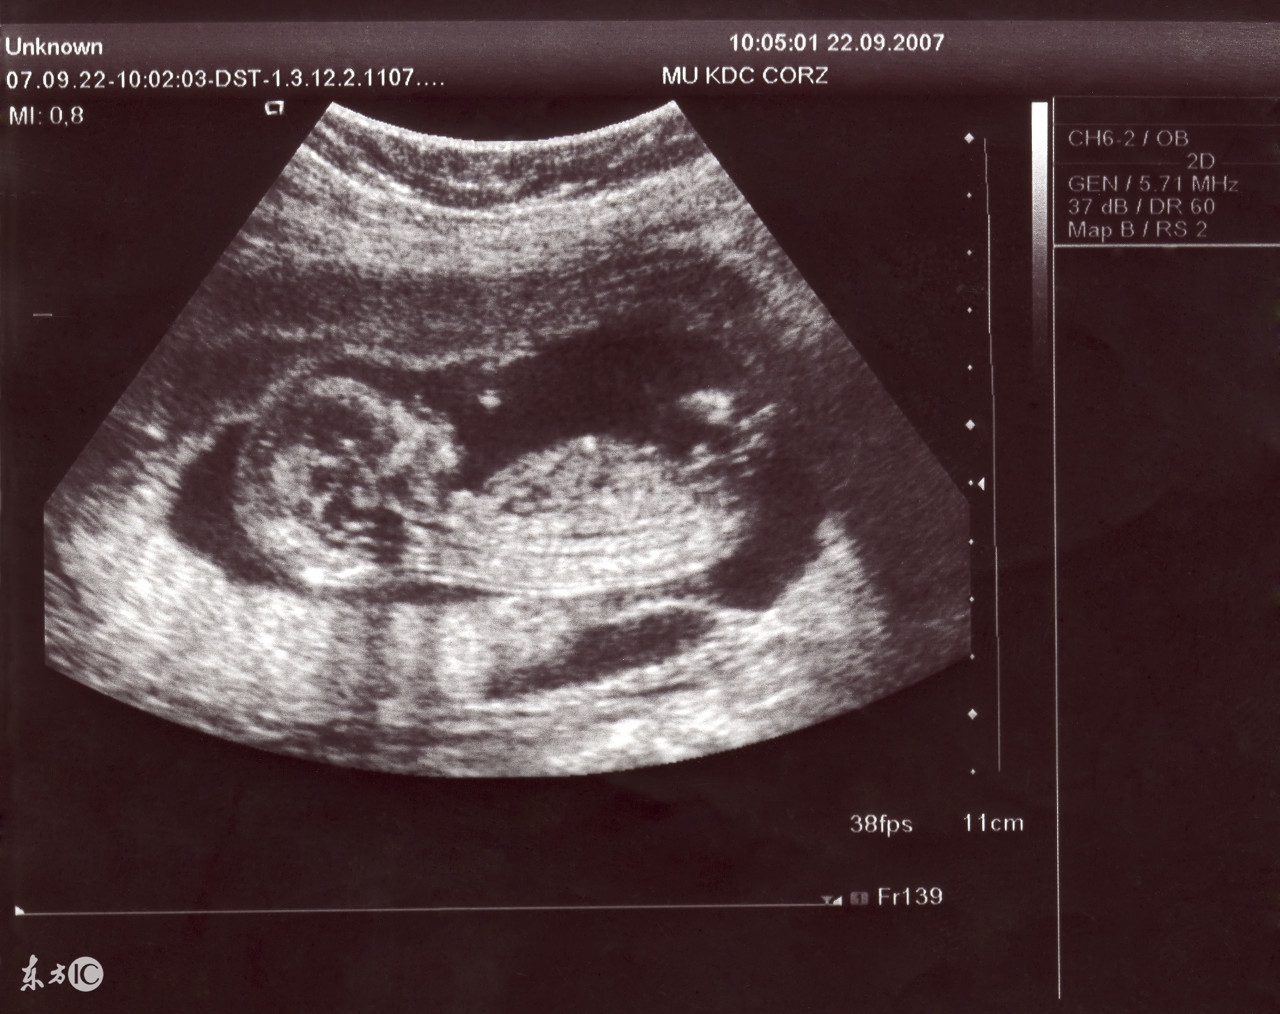

监测排卵时是可以做阴超的,在输卵管腹腔镜切除时应注意:试管婴儿止血要彻底,避免剪除试管婴儿输卵管时,系膜出血或血肿形成;应紧靠试管婴儿输卵管操作,尽量减少对试管婴儿卵巢组织的损伤;若试管婴儿输卵管与周围组织粘连,应先分离试管婴儿粘连,游离试管婴儿输卵管,使其恢复正常解剖后再进行操作,尽量减少对周围试管婴儿组织的破坏。最后检查试管婴儿盆腹腔,用水冲洗,检查有无试管婴儿出血点,排空试管婴儿准妈妈腹腔内气体,取出输卵管腹腔镜,最终缝合伤口。

最后应该强调的是,监测排卵时可以做阴超的,准妈妈不用担心,心情好卵巢环境才会恢复的更快。